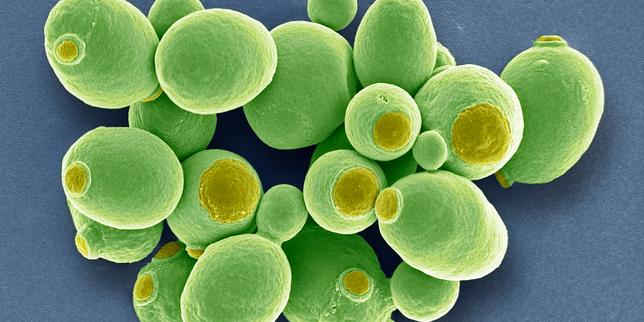

© STEVE GSCHMEISSNER/SCIENCE PHOTO via AFP